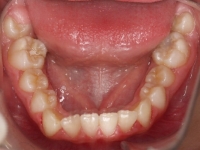

El paciente A.J. de 11 años, acude a nuestra consulta con apiñamiento maxilar importante. El canino lateral (12) está en mordida cruzada. Presenta una Clase II molar y canina, y la línea media está desviada. Se realizó un tratamiento con brackets autoligables metálicos de smartclip 022. La duración del tratamiento fue de 22 meses.

El paciente actualmente ha terminado el tratamiento con brackets y lleva una contención fija de 2-2 en maxilar y 3-3 en mandibular; para complementar también lleva una férula ESSIX durante la noche.